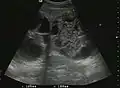

-

Liver cyst -

The ultrasound appearance is a well defined lesion, with very thin, almost unapparent walls, without circulatory signal at Doppler or CEUS investigation. The content is transonic suggesting fluid composition. The presence of membranes, abundant sediment or cysts inside is suggestive for parasitic, hydatid nature. Posterior from the lesion the acoustic enhancement phenomenon is seen, which strengthens the suspicion of fluid mass. They typically displace normal liver vessels but no vascular or biliary invasion occurs.